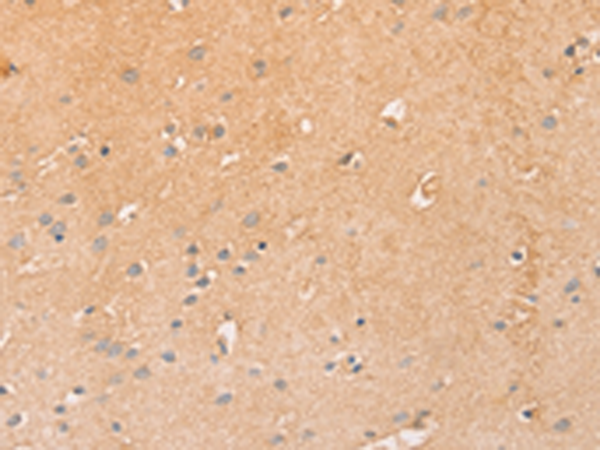

分类: 科研抗体货号: P11628别名: LEC; LMC; NCC4; CKb12; HCC-4; LCC-1; Mtn-1; NCC-4; SCYL4; ILINCK; SCYA16应用: WB,IHC反应种属: Human

分类: 科研抗体货号: P11640别名: T10应用: WB,IHC反应种属: Human

分类: 科研抗体货号: P11626别名: KRS1; MST2/KRS2; MST1; YSK3; TIIAC应用: WB,IHC反应种属: Human, Mouse

分类: 科研抗体货号: P11638别名: CD327; CD33L; OBBP1; CD33L1; CD33L2; CDW327应用: WB,IHC反应种属: Human

分类: 科研抗体货号: P11636别名: LY94; CD335; NKP46; NK-p46应用: WB,IHC反应种属: Human, Mouse

分类: 科研抗体货号: P11664别名: CIB; CIBP; KIP1; PRKDCIP; SIP2-28应用: IHC反应种属: Human, Mouse, Rat

分类: 科研抗体货号: P11634别名: CD30; Ki-1; D1S166E应用: IHC反应种属: Human